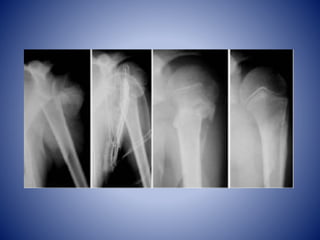

HUMERO

• Hueso mas grande del M.S

• Se articula con la escápula por la articulación

Glenohumeral (sinovial esferoidea), y con el

radio y cúbito por la articulación del codo

(sinovial en Bisagra)

• Está formado por una porción proximal, una

diáfisis y una porción distal

Humero Proximal

• Cabeza, cuello, tubérculo mayor y menor

• Cabeza: forma esférica se articula con cav.

Glenoidea

• Cuello Anatómico: formado por el surco que

circunscribe la cabeza y separa ésta de los

tubérculos.

• Cuello quirúrgico: parte estrecha distal a los

tubérculos y a las crestas que descienden de

ellos. Sitio de frecuente fractura.

• Tubérculos (tuberosidades): marcan la unión

de la cabeza y el cuello con el cuerpo.

• Tubérculo mayor (Troquiter): borde lateral del

húmero.

• Tubérculo menor: (Troquín): proyección

anterior

• Los tubérculos se separan entre sí por el surco

intertubercular (surco bicipital)

Cuerpo Húmero

• 2 rasgos:

• Tuberosidad deltoidea: lateral para inserción

musculo deltoideo.

• Surco oblicuo del nervio radial: cara posterior,

aloja al N. radial y A. braquial profunda entre

las cabezas medial y larga y luego lateral del

M. tríceps braquial

• Inferiormente se ensancha en las crestas

supracondíleas medial y lateral.

Húmero Distal

• Epicóndilo medial y lateral

• Tróclea

• Cóndilo humeral

• Fosa olecraneana (Olecranon)

• Fosa coronoidea

• Fosa radial

• 2 articulaciones distales: cóndilo humeral lateral

para el radio, trócleo medial para la escotadura

troclear del cúbito.